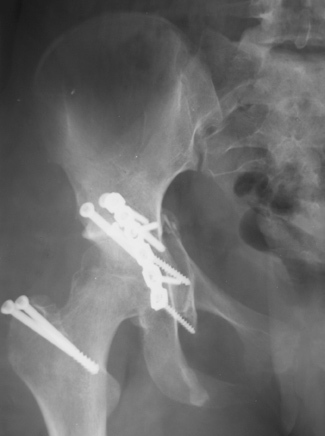

30/11/04 |  30/11/04 |  30/11/04 |  14/12/04 |  14/12/04 |  14/02/05 |  14/02/05 |  21/02/05 | Уважаемые коллеги! Случилось вторичное смещение вертлужной впадины после операции. Посоветуйте, что делать. Пациентка 18 лет. Травма 19.11.04. D.s.: Закрытыый Т-образный высокий перелом правой вертлужной впадины. Закрытый перелом м\мыщелкового возвышения левой б\берцовой кости. 9.12.04 операция - открытая репозиция, остеосинтез переломам вертлужной впадины. 30.12.05 выписаны на амбулаторное лечение с рекомендациями не вставать на правую ногу. 14.02.05 при контрольном осмотре на Р-граммах выявлено вторичное смещение передней колонны. Клинически подвывиха нет, имеется умеренная приводящая контрактура правого тазобедренного сустава, гипотрофия мышц н\конечностей. Госпитализирована в травмотделение. Выполнено КТ. Имеется смещение передней колонны кнутриЮ диастаз 8 мм. Посоветуйте пожалуйста, что предпринять в данной ситуации.

У больной имеется диастаз лонных и седалищных костей, то есть "разорвано" тазовое кольцо. В перспективе возможно образование ложного сустава на уровне основания лонной кости с болевым синдромом, поскольку седалищная кость не срастется.

2. ограничить двигательную активность до 6 мес. (не нагружать ногу, носить тазовый корсет-пояс и т.д.) с контролем сращения. Вроде бы на Р-граммах угадывается слабая тень формирующегося костного мостика по l. iliopectinea, это место в представленные срезы КТ не попало. Если к 6 мес. ничего не нарастет, то см. пункт 1.